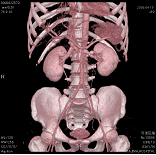

その結果、単に画像が速く綺麗に撮れるということにとどまらず、従来はできなかった縦方向の画像(実際に撮影しているのではなく、検査後にコンピュータで計算させて

上下方向の画像を作成するもの:MPR画像という)や、立体的な3次元画像なども従来よりもはるかに有用なものとして活用できるようになっております。